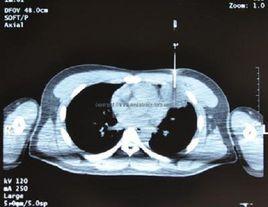

(二)CT引導經皮穿刺肺活檢診斷肺部疾患CT引導下穿刺適用範圍廣,臨床套用最多。CT橫斷層掃描有良好的空間解析度和密度解析度,可準確顯示病灶的大小、位置及內部情況,以及與血管等周圍結構的解剖關係,尤其適用於定位難度大、病灶在肺門及縱隔附近者。當腫塊與肺不張、阻塞性肺炎混合後,有時需行增強掃描才能確定腫塊的實際大小。方法是指先作CT掃描確定病灶最佳的穿刺點,進針深度和角度,而後進行穿刺活檢。常規CT下不能直接觀察進針狀況,必須在確定進針點後估算進針深度及進針方向,進針後再次掃描確認後方可行穿刺活檢。

CT引導下穿刺精確度高,對於0.5~1cm的病灶也可在CT導引下成功活檢。因此對常規方法未能確診的肺部結節病變、空洞病變、雙肺瀰漫性病變及縱隔肺門占位病變,套用CT引導下肺穿刺抽吸和切割針活檢能取得較滿意結果。尤其直徑≤2cm肺部結節活檢的準確性較高而併發症較低,可作為肺內孤立性小結節灶定性診斷的首選方法,其操作簡單、安全、可靠。